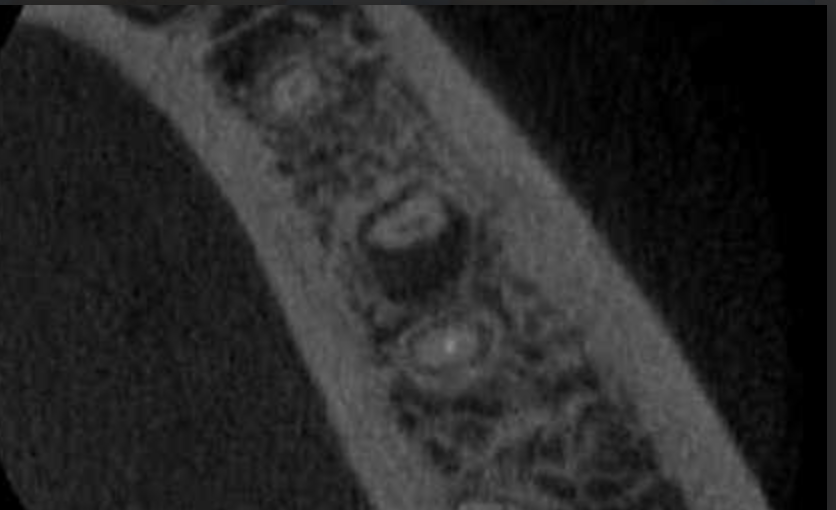

Vertical root fracture